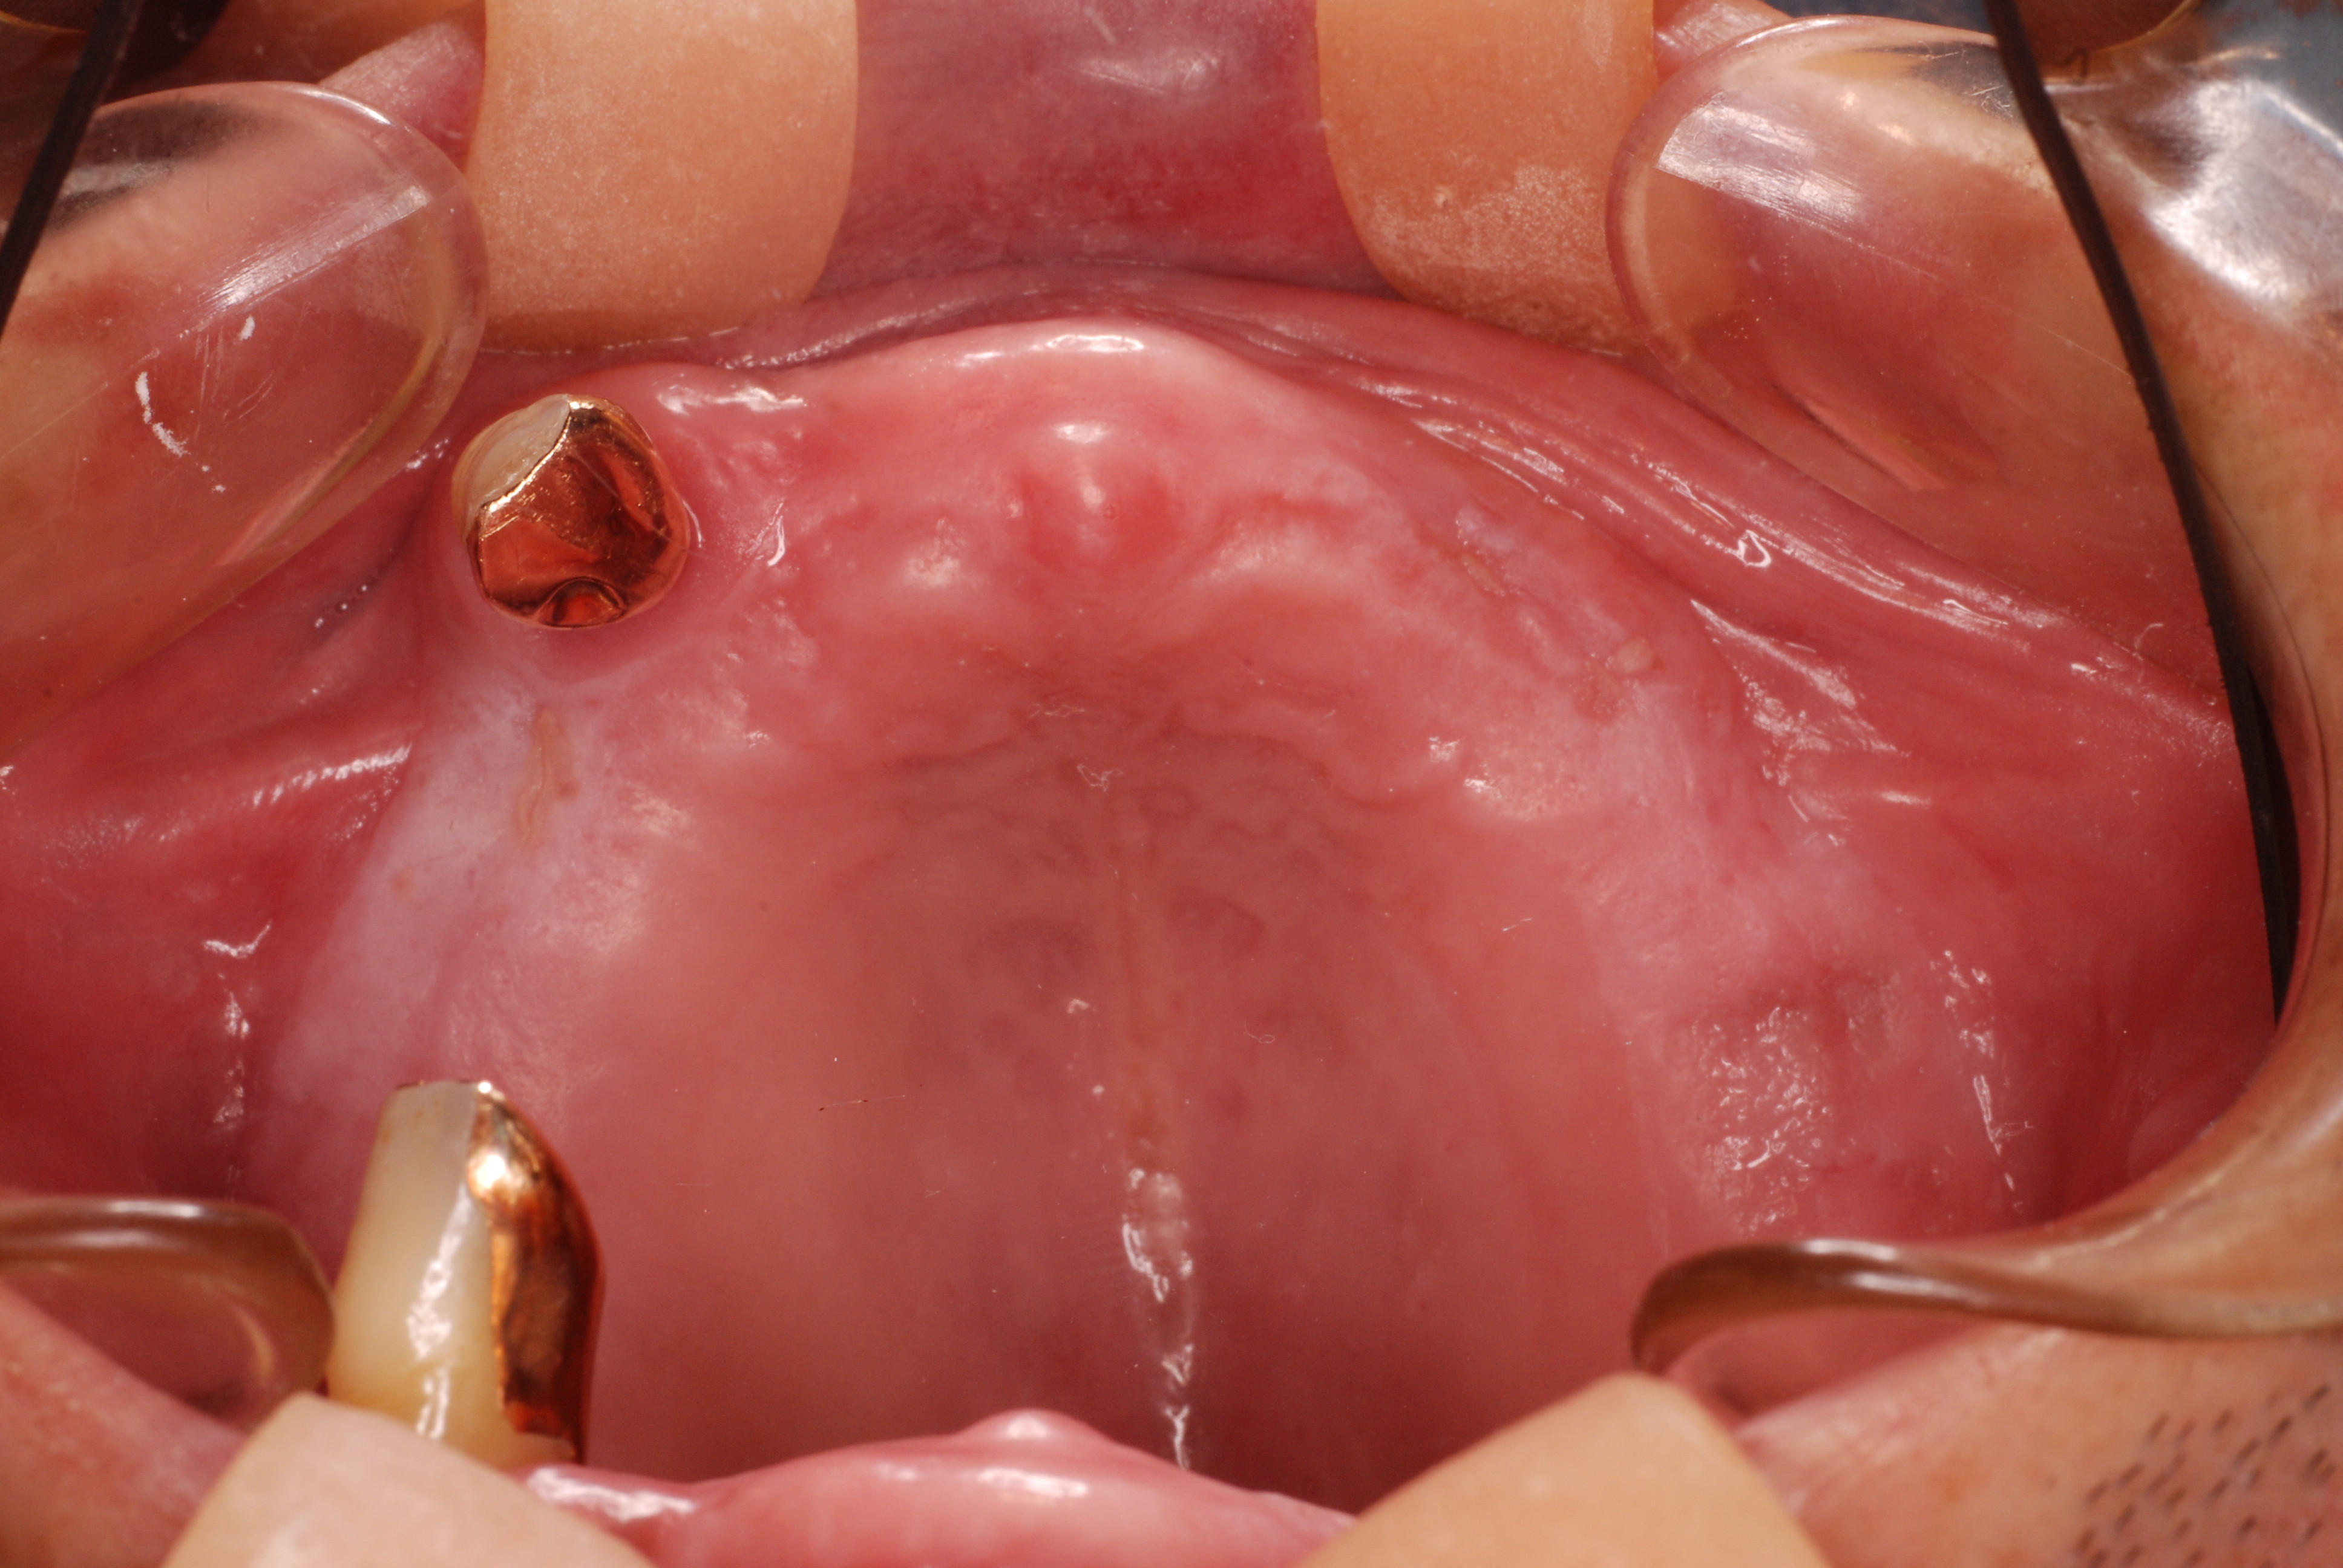

現実を見ればお口の中には“異物”である金歯、銀歯、セラミック、インプラントのオンパレードです。

これ等のものは、異物です。無い方が病気にならず健康でいられるのです。

現在は材料も最高級品、外注する職人さんも最高級品を目指してお願いしています。

銀歯の下はばい菌だらけです。こういうのはよくあります。取り残しですね。![treatment_05[1]](https://livedoor.blogimg.jp/netdental/imgs/3/a/3ad019d0-s.jpg)